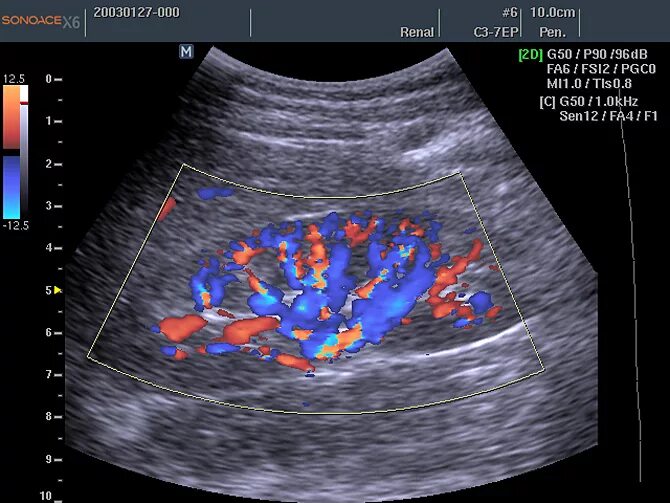

Нефросклероз почек на узи что это такое